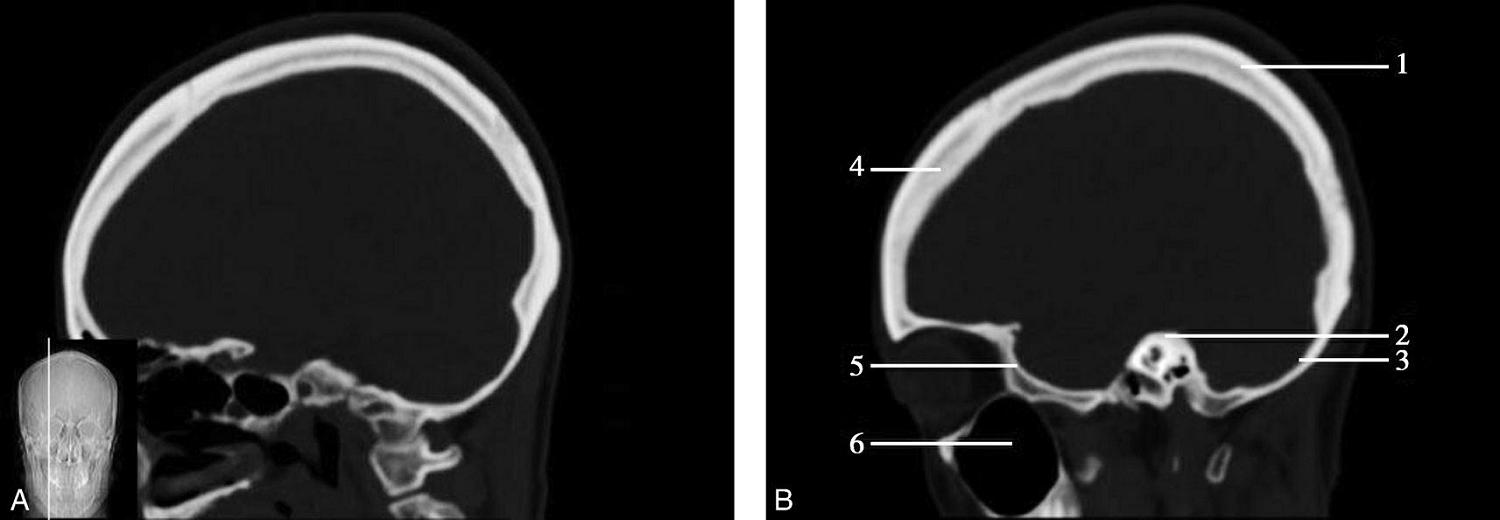

重要结构:胼胝体、垂体、中脑导水管、扣带回、中央沟、第三脑室、斜坡(图1-2-59、图1-2-60)。

图1-2-59 正中矢状面CT

A.矢状面;B.矢状面标注

1.中央沟;2.扣带回;3.胼胝体体部;4.侧脑室;5.中脑;6.胼胝体膝部;7.穹隆;8.第三脑室;9.胼胝体压部;10.垂体;11.中脑导水管;12.第四脑室;13.脑桥;14.蝶窦;15.斜坡;16.小脑扁桃体;17.延髓

图1-2-60 正中矢状面骨窗CT

1.顶骨;2.枕骨;3.斜坡;4.额骨;5.蝶鞍

此层面可显示胼胝体全貌,它位于层面中央区域,是呈上凸下凹的弧形结构,由前向后分为嘴、膝、体和压四部分。扣带回环绕胼胝体上方,扣带沟位于扣带回的上方。大脑半球中部和后部分别可见较深且恒定的中央沟和顶枕沟。中央沟为是额叶顶叶分界标志。

胼胝体下方为侧脑室及穹窿,第三脑室借穹窿与前上方的侧脑室体部分开,背侧丘脑的内侧面以及中脑顶盖分别为第三脑室的外侧壁和底。第三脑室向前籍室间孔与侧脑室相通,向下经中脑导水管通第四脑室。中脑腔狭窄呈管状,即称为中脑导水管,中脑导水管畸形,常见者为导水管的分叉畸形和狭窄,其次可见中脑导水管膈膜,造成先天性脑积水。

脑干由中脑、脑桥和延髓组成,自第三脑室底向下后稍斜行,移行于颈髓。由上至下,脑干腹侧可见脚间池、桥前池和延髓池,脑干背侧可见大脑大静脉池、四叠体池和小脑延髓池。

垂体位于蝶鞍内,其前部为腺垂体,后上部分为神经垂体。垂体下方为鞍底及蝶窦,上缘因鞍膈存在而平直,垂体借垂体柄向上连于丘脑下部。垂体的前上方见视交叉和视束。斜坡作为前颅窝底的重要组成部分与多个重要结构相比邻,矢状位呈三角形,颅内肿瘤或颅外鼻咽部恶性肿瘤均可侵犯至此,原发肿瘤常见为脊索瘤。小脑幕居枕叶和小脑之间,向后下连接窦汇,向前至中脑后方游离,称小脑幕切迹。小脑幕下方为小脑扁桃体。成年人小脑扁桃体下缘由枕骨大孔向下疝入椎管超过5mm称为Chiari畸形,以矢状位显示最佳。